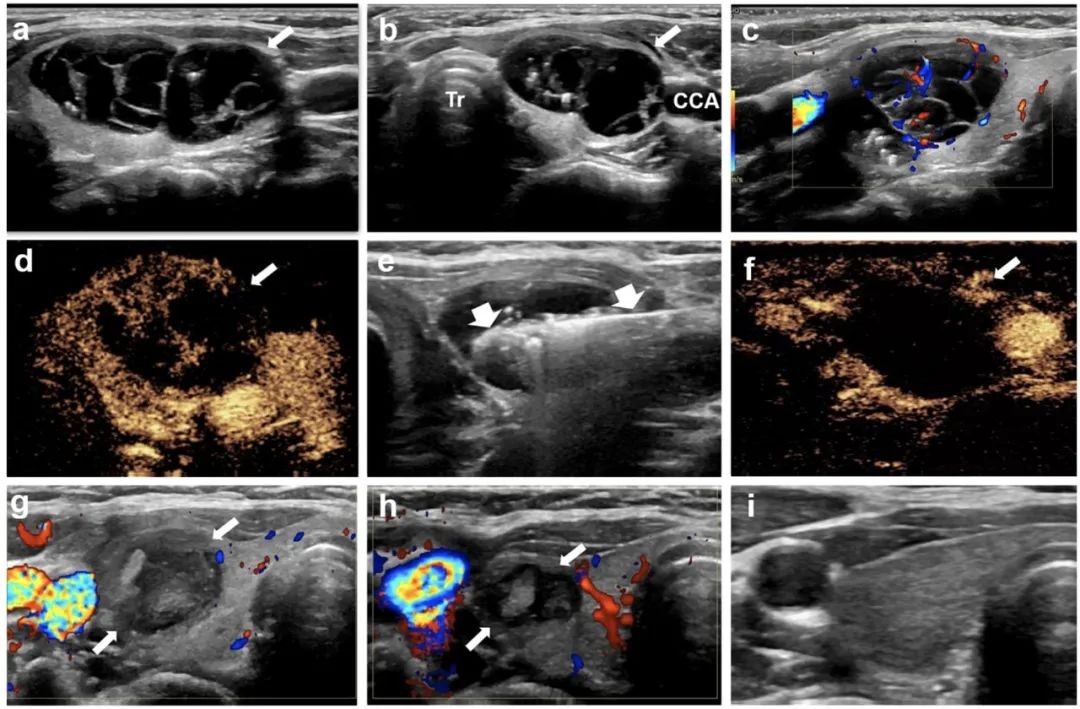

针对该问题,石文媛主任团队开创性地将微波消融技术应用于儿童良性甲状腺结节的治疗。连续分析了2018年1月至2021年12月在北京儿童医院接受经皮微波消融治疗的有症状良性甲状腺结节患儿25名,共 34枚结节。所有患儿均随访半年以上(中位随访时间12个月,范围6 - 48个月)。结果显示:经皮微波消融治疗后,结节体积逐渐减小(微波消融前中位体积5.86 mL,末次随访评估中位体积0.34 mL),末次随访评估体积缩小率达到85.03%,技术有效率达91.2%。结节相关压迫症状、美容相关问题均得到显著改善。术后一个月随访甲状腺功能维持在正常范围之内,提示微波消融在灭活甲状腺结节的同时不影响正常甲状腺功能。

甲状腺右叶囊性为主结节,微波消融后3年,病灶完全消失